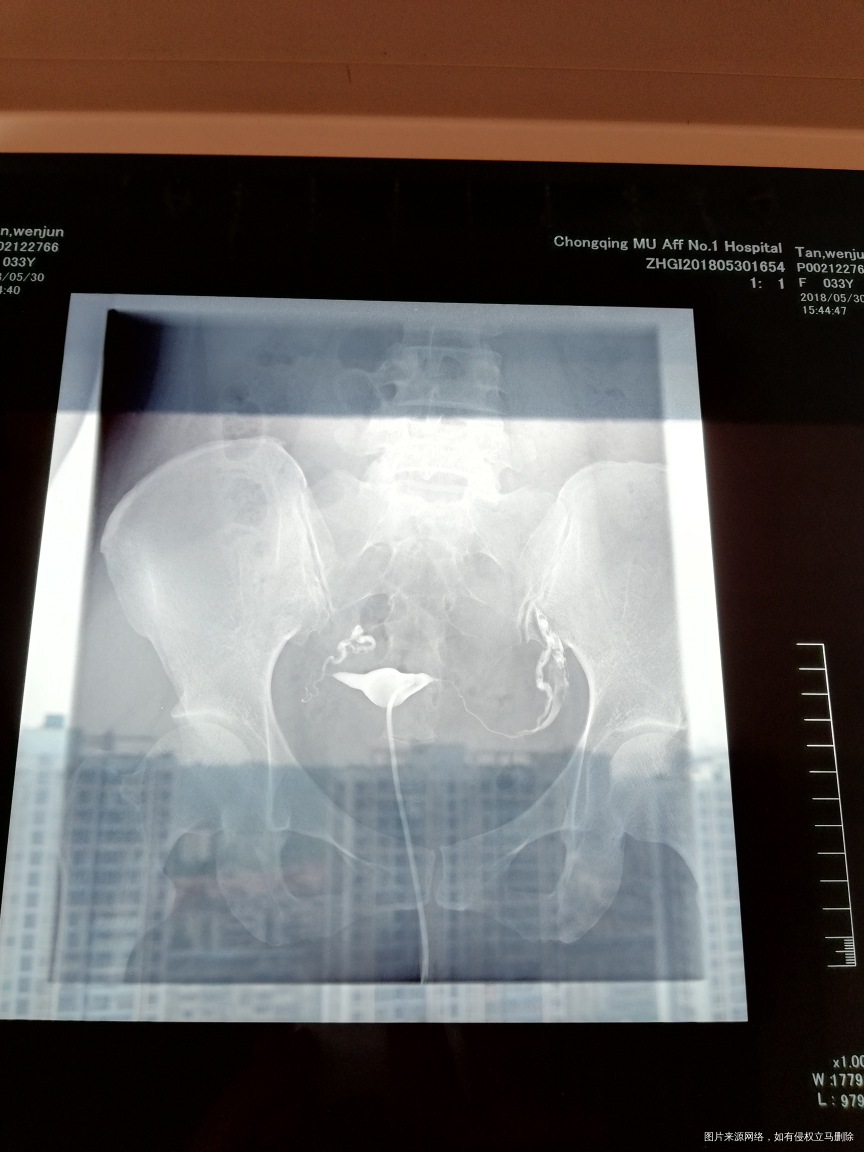

麻烦帮我看看输卵管碘水造影检查结果。我这样怎么治疗,是不是需要做试探婴儿

您好,输卵管通畅的就可以怀孕试试,如果确实怀孕困难可以选择腹腔镜手术,或者试管婴儿。

双侧输卵管通的!上举,可以试孕三个月看看。